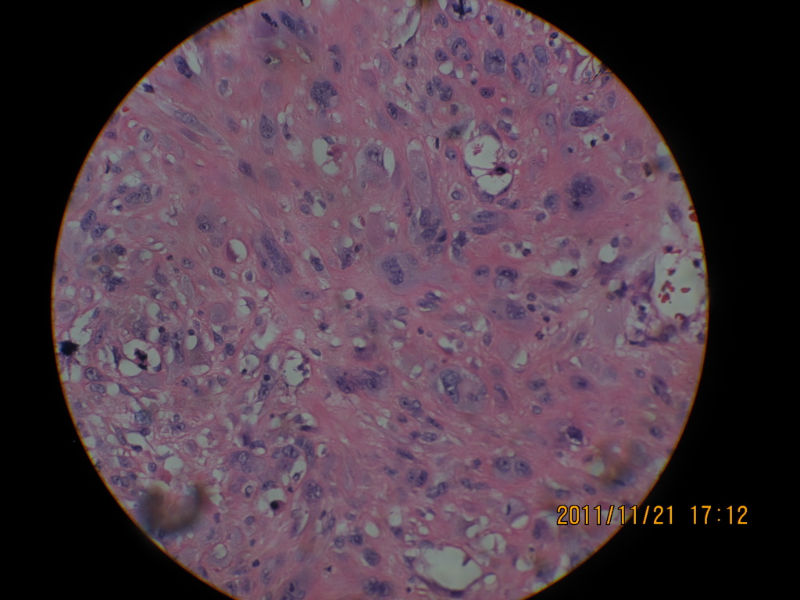

男性,82岁,声带肿物

图1

图2

图3

图4

图5

图6

图7

图8

图9

图10

图11

图12

图13